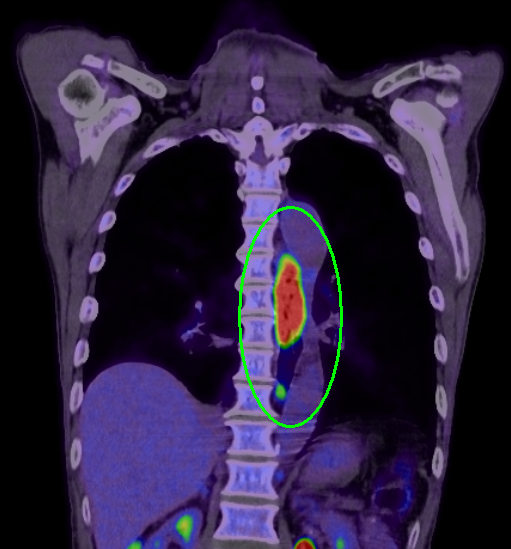

進行度を判断するための検査では、CT検査(PET/CT検査)、MRI検査、超音波内視鏡検査などを組み合わせて、がんの深さやリンパ節および周辺臓器への転移がないかを診断します。

PET/CT検査画像